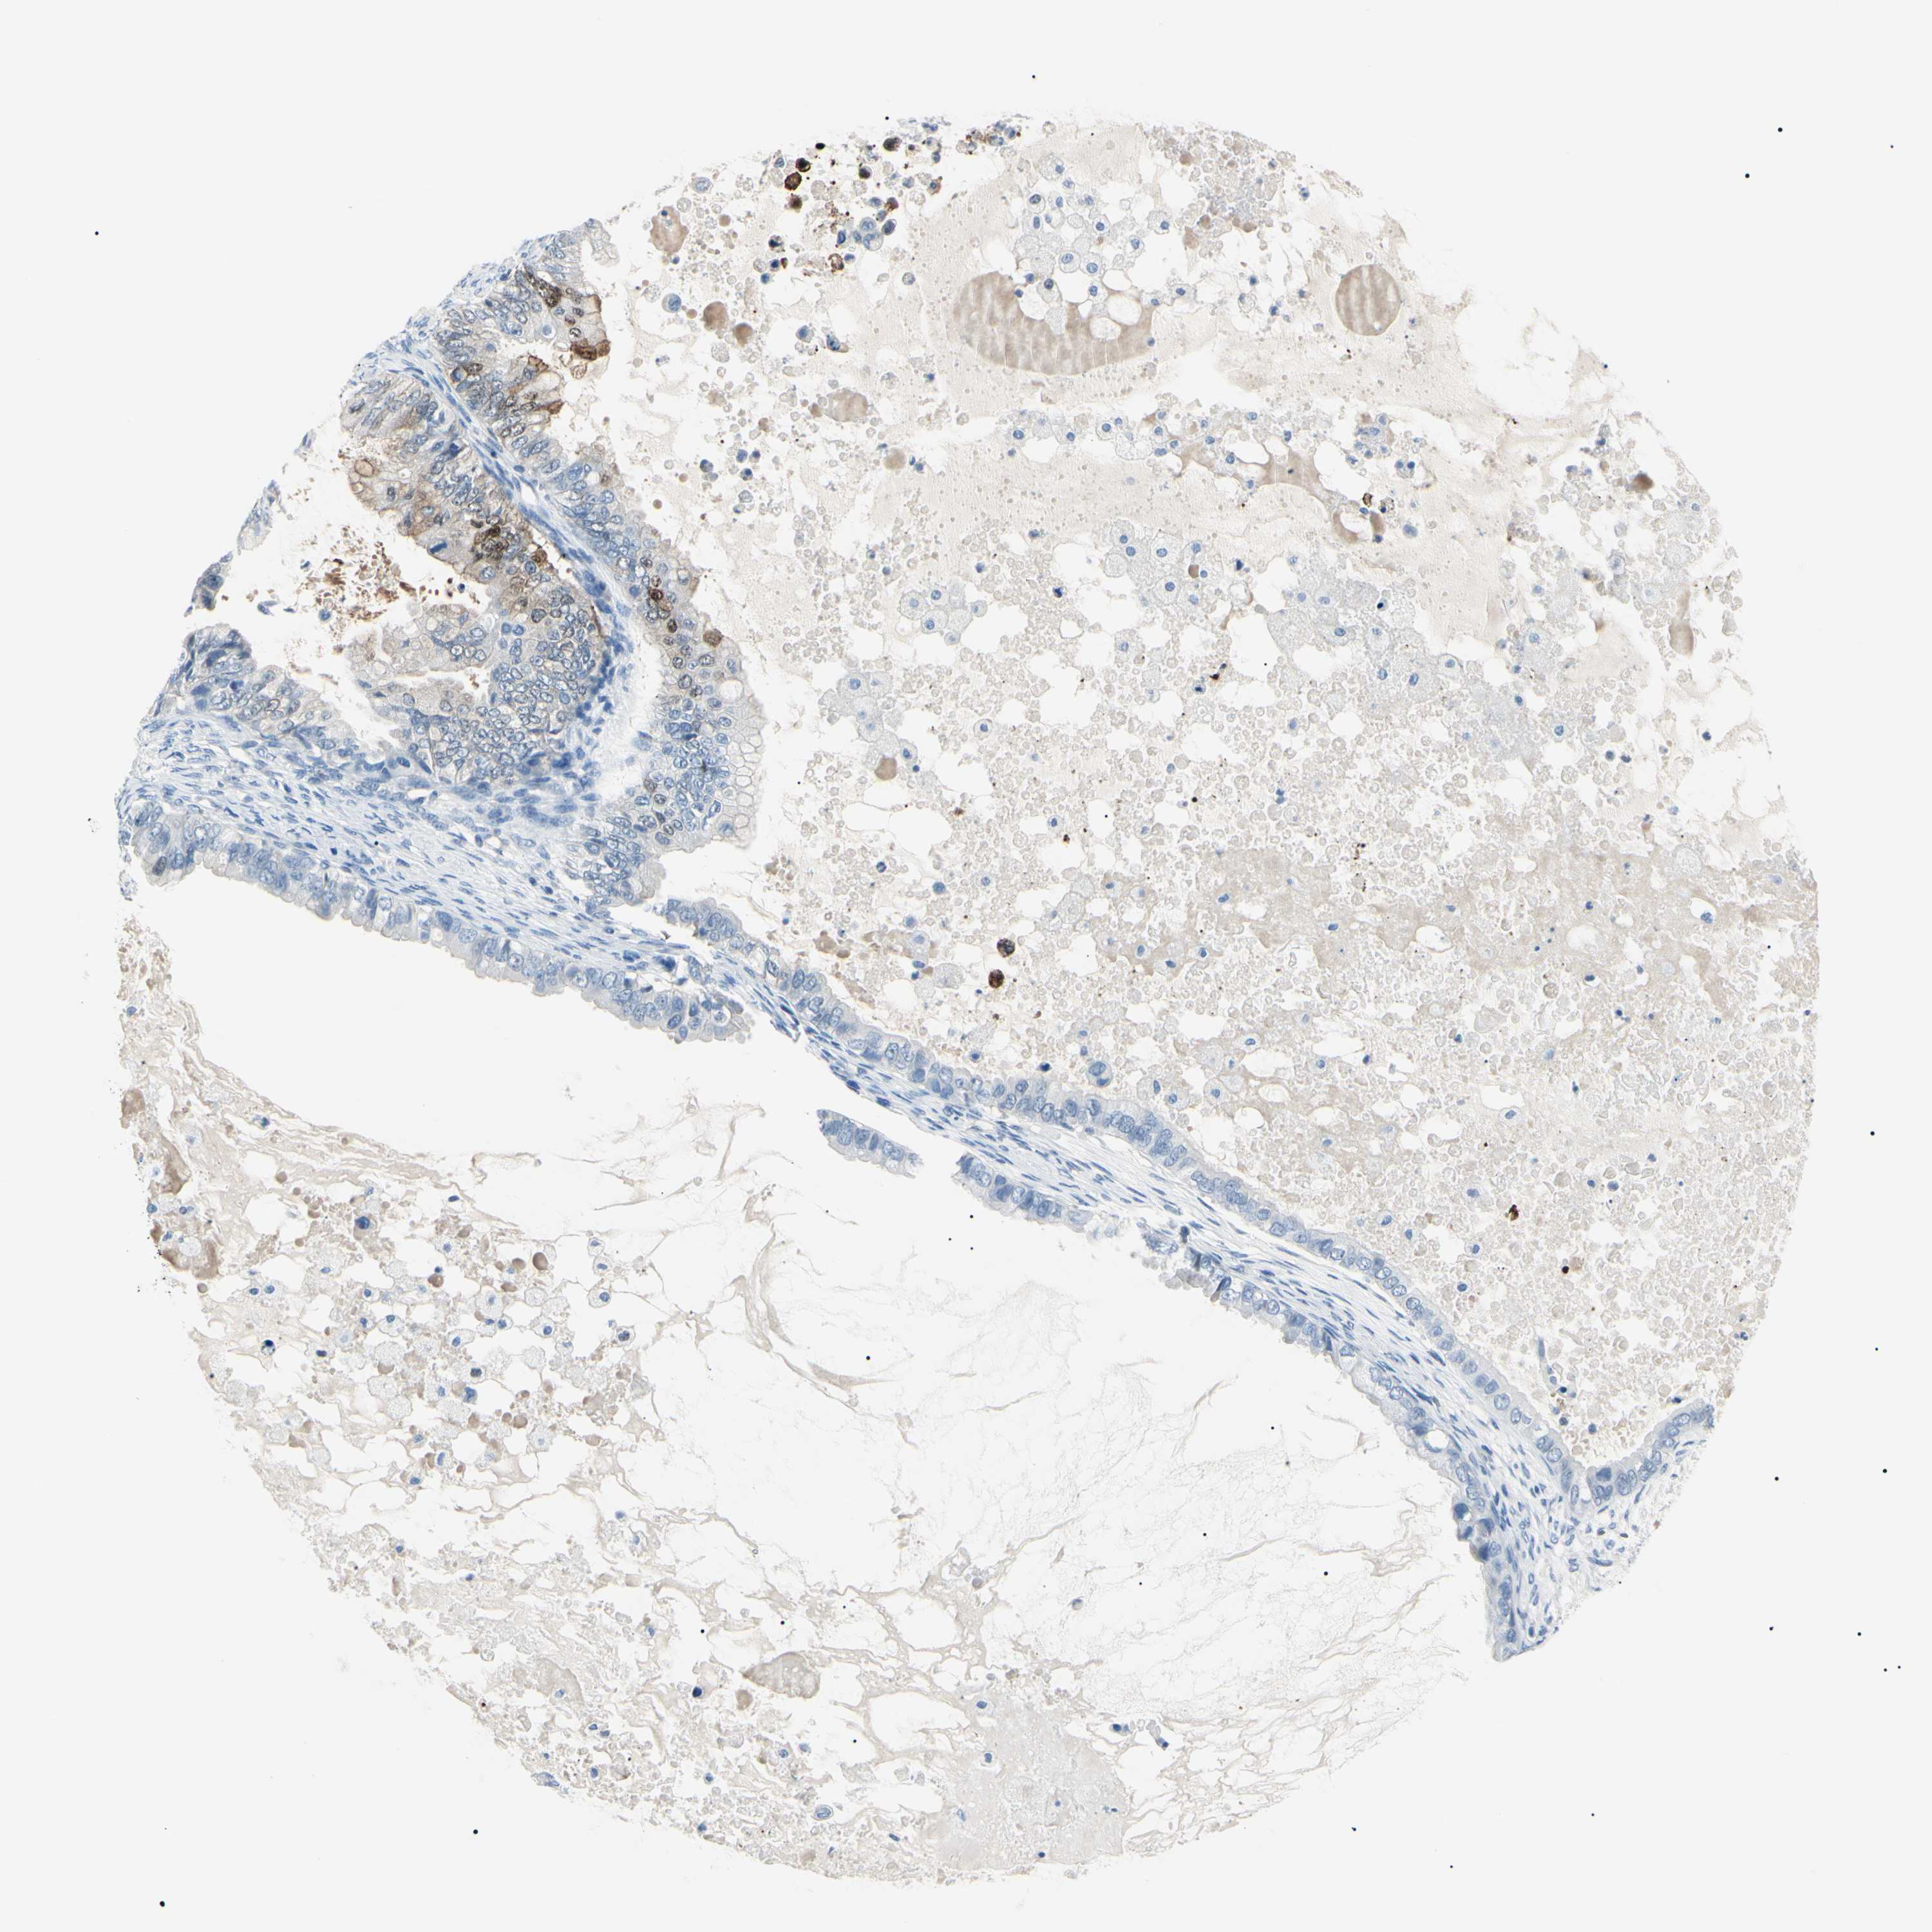

OVARIAN CANCER - Protein expressioni

A mouse-over function shows sample information and annotation data. Click on an image to view it in a full screen mode. Samples can be filtered based on level of antibody staining by selecting one or several of the following categories: high, medium, low and not detected. The assay and annotation is described here.

Note that samples used for immunohistochemistry by the Human Protein Atlas do not correspond to samples in the TCGA dataset.

Antibody stainingi

Antibody staining in the annotated cell types in the current human tissue is reported as not detected, low, medium, or high, based on conventional immunohistochemistry profiling in selected tissues. This score is based on the combination of the staining intensity and fraction of stained cells.

Each image is clickable and will lead to virtual microscopy that enables deeper exploration of all samples and also displays staining intensity scores, fraction scores and subcellular localization as well as patient and tissue information for each sample.

Antibody HPA001550

Antibody CAB010102

Staining

High

Medium

Low

Not detected

Intensity

Strong

Moderate

Weak

Negative

Quantity

>75%

75%-25%

<25%

None

Location

Nuclear

Cytoplasmic/membranous

Cytoplasmic/membranous,nuclear

Carcinoma, endometroid

Cystadenocarcinoma, serous, NOS

Cystadenocarcinoma, mucinous, NOS

Carcinoma, NOS